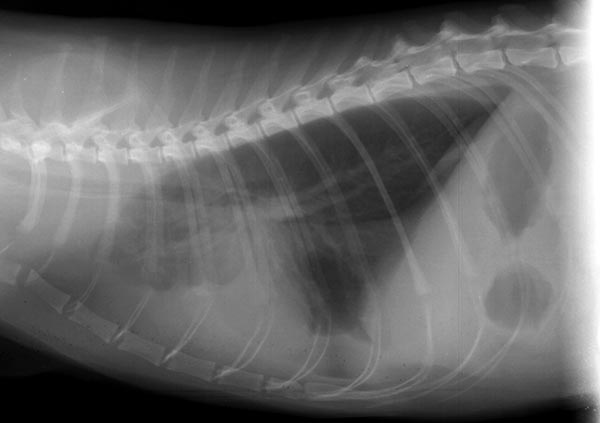

翻译:祁海丽;校对:石慧18 A 6-year-old intact female Labrador retriever dog presents with a...